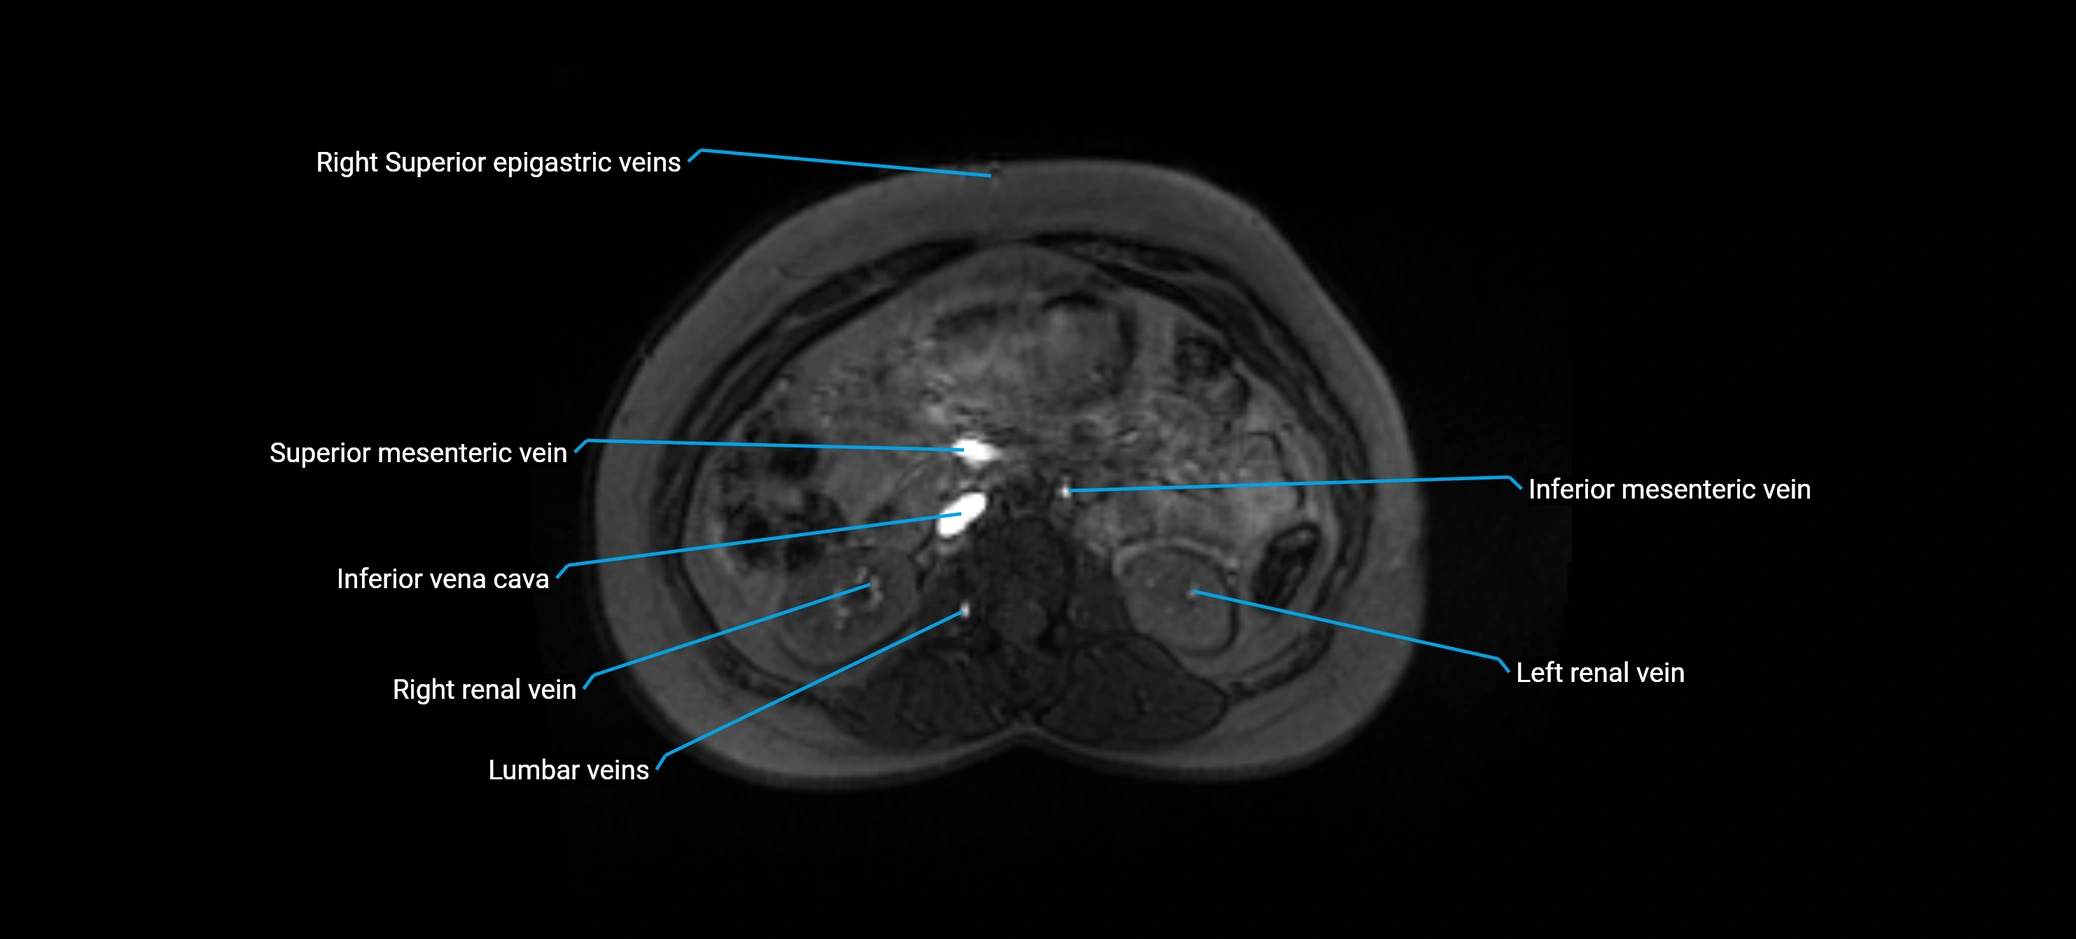

MRI image

image